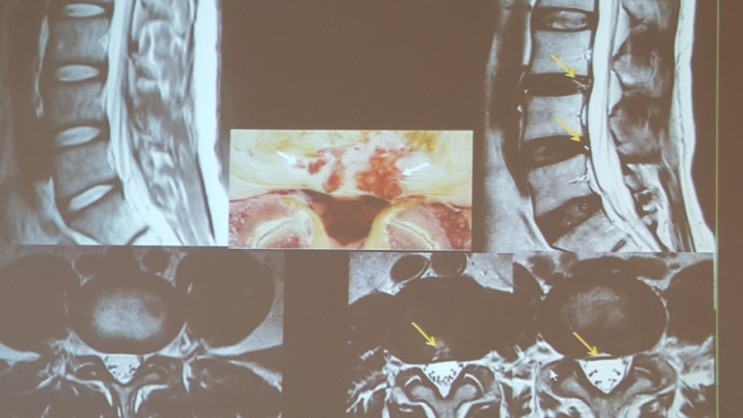

이런 환자들에게 MRI 등의 정밀 검사를 시행해 보면 허리 한두 마디에 소위 ‘검은 디스크’가 종종 관찰되곤 한다. 이른바 추간판 내장증 (degenerative disc disease)이라고 불리는 이 소견은 다리에의 통증 없이 허리만 매우 아픈 상태를 말한다. 위의 사례와 같이 추간판 높이가 정상인 못지않게 유지되는 경우도 있어 그 정도를 X-ray만으로 판단하기는 어렵다.

MRI 상 추간판이 검게 변하여 보이는 것은 디스크 내 수핵 물질의 탄성 저하를 나타내는 것으로 대개 20세 이후에는 남녀노소 누구라도 허리 한 마디쯤에 나타날 수 있는 노화 과정의 일부이다. 디스크의 탄성이 저하되면 움직임이 불안정 해지기 시작하여 척추 후관절에도 조금씩 변화가 일어 날 수 있으며 후방 섬유테에 스트레스가 높아져 부분적으로 찢어 질 수도 있다. 섬유테에 구멍이 크게 생겨 수핵 물질이 신경이 있는 쪽으로 터져 나오면 허리 통증과 함께 엉덩이와 다리 쪽으로 저림과 통증이 함께 느껴지는 디스크 탈출증의 증세를 보이게 되지만, 다른 경우 섬유테의 부분적 파열과 함께 수핵이 바깥으로 완전히 빠져 나오지 않은채 아물고 다시 찢어지기가 반복되기도 한다. 이런 경우 다리 증세 보다는 허리나 엉치 통증이 주된 증상이며 정형외과나 통증의학과 의원에서 MRI 검사 없이 단순 X-ray 검사 정도 만으로 진단하고 치료 받는 경우 디스크 초기 증상이라거나 협착증이 보인다는 등의 추정 진단을 듣게 될 수 있다.